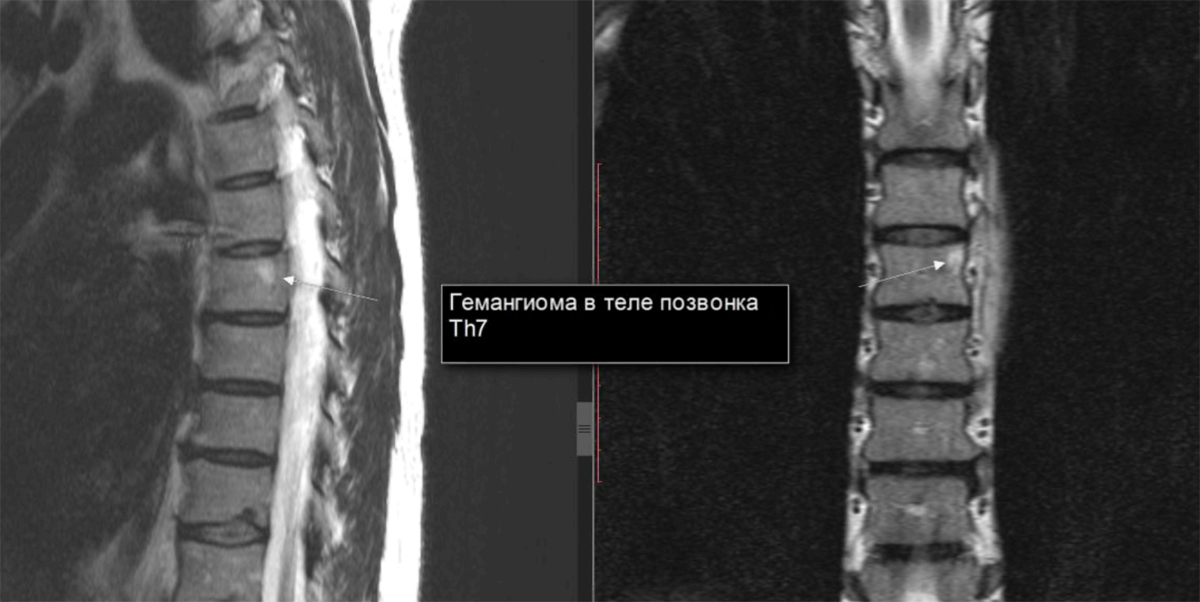

Позвонок Th10: анатомия и фото медицинских иллюстраций